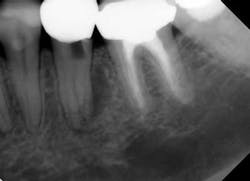

Knowing when a tooth is restorable (and when it is not) is a key diagnostic skill and a predictor of future endodontic success. Taken at face value, this concept seems obvious, but, for example, assessing when a tooth is vertically fractured and/or has a risk of future vertical fracture is not always clear, as is illustrated by the case shown in Fig. 1.